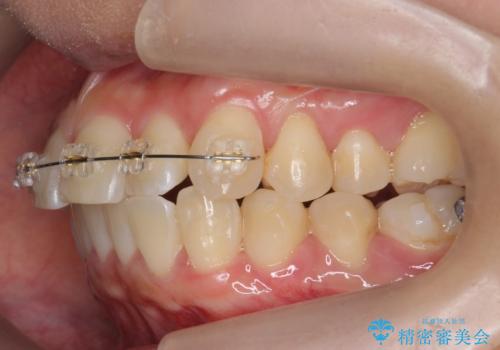

上のワイヤー矯正を半年ほど行い反対咬合を改善してから、上下インビザライン治療を行いました。

左上の反対咬合になっていた歯の頬側咬頭は、すでに削れて短くなっていましたがそのまま並べています。